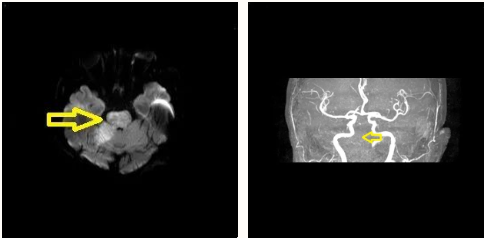

手术非常成功,王大爷恢复良好,顺利回归正常生活。2023年2月1日,王大爷因房颤导致栓子脱落造成脑栓塞再次入院治疗,据家属描述老人未遵医嘱自行停服抗凝药物已达半年。由于栓塞面积大,而且位置靠近重要功能区,这给手术带来了极大的风险和难度。

情况危急,赵主任与团队反复研究并征得家属同意后,立即进行手术治疗。当日13:00王大爷在全麻下行急诊支架取栓手术,13:54取栓手术成功。术中取出大量栓子, 基底动脉恢复畅通。

术后2小时老人恢复清醒,第二天拔出气管插管,转危为安。现在的王大爷神志清醒,问答合理,四肢活动自如,每次看到为他做了两次取栓手术的赵主任都感动不已!